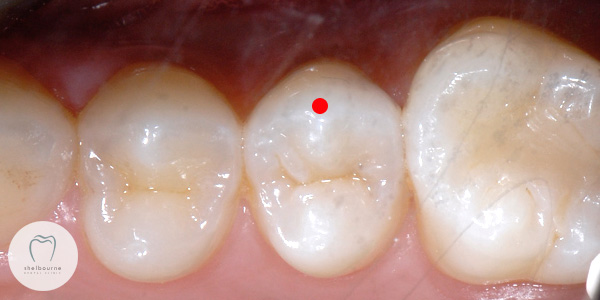

Have a look at this picture. All looks pretty good doesn’t it? Until, I look at the x-ray of these same teeth. I’m specifically looking at the tooth with the red dot on it – Suddenly things aren’t so pretty….